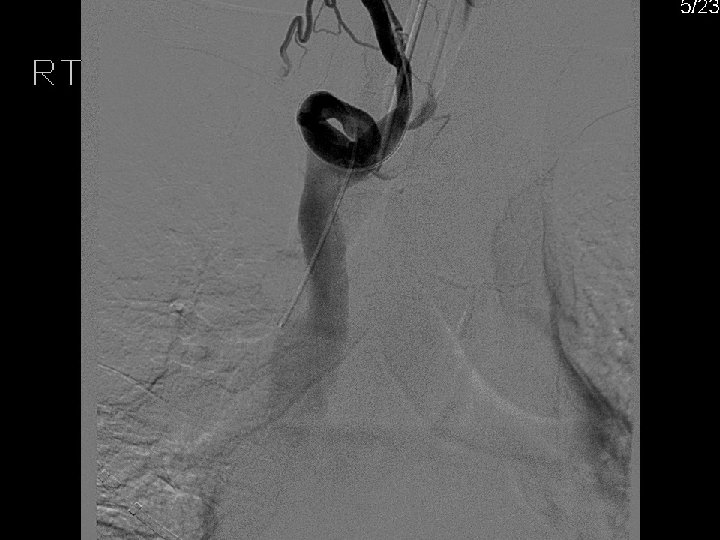

Amplatz GOOSE NECK® Snare Kit (ev 3) • Nitinol cable with gold plated tungsten loop & platinum-iridium marker band. • 90 degree snare loop. • Wide range of loop diameters: 5 mm – 35 mm. • Catheter length = 102 cm. • Snare length = 120 cm.

EN Snare® (Angiotech / Hatch Medical) • Three nitinol loops with interwoven platinum strands for radiopacity and radiopaque band. • Angled catheter tip (15°) • Wide range of loop diameters: 6 mm. – 45 mm. • Catheter length = 100 cm. Snare length = 120 cm.

EXPRO Elite™ Snare (Radius Med. Tech. ) • Helical shaped loop made from cobalt chromium makes loop and tip radiopaque. • Wide range of loop diameters: 5 mm – 35 mm. • Snare & catheter length = 150 cm. (integrated system). • Distributed by both Vascular Solutions and by Abbott.

Snare Retrieval En. Snare